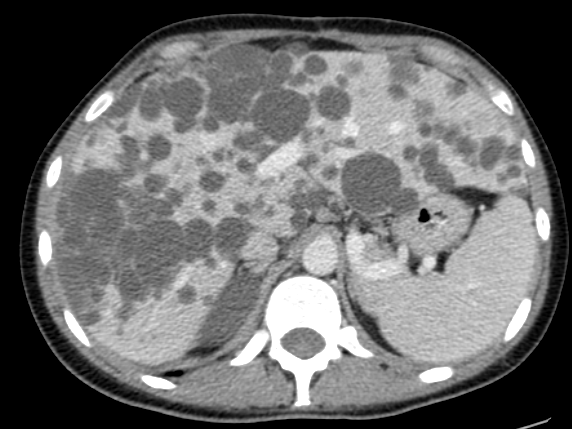

Fasceitis Necrotizante

Antonio Alvarado Armuelles, Alonso Bósquez Barría